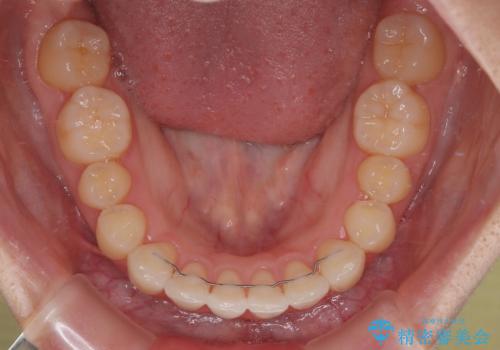

- 矯正装置

- 審美装置

- 治療期間

- 1年1ヶ月

舌の突出癖により、出っ歯仕上がりとなる可能性がありましたが、舌のトレーニングを頑張っていただき、1年強で終えることができました。

- 矯正治療後の保定が不十分だと後戻り(元の位置に戻ろうとする動き)をします